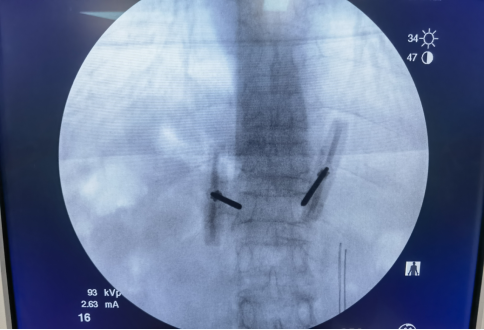

透視定位穿刺位置的好壞,是決定手術(shù)質(zhì)量的關(guān)鍵點(diǎn)。術(shù)前透視定位傷椎正位:從頭往尾,最后一節(jié)有肋骨的為T12,從尾往頭,兩髂嵴聯(lián)線齊第四腰椎棘突?!叭L(zhǎng)四翹五肥大”:一般L3橫突較長(zhǎng),L4橫突短而上翹,L5橫突較肥大。側(cè)位:楔形變,雙凹形變椎體為傷椎。例:T12上肋骨沒發(fā)育。注意:L5骶化,S1腰化,T12無肋骨的特例。以椎弓根途徑為例,皮膚進(jìn)針點(diǎn),為穿刺針針尖離椎弓根眼外緣1.5cm左右。經(jīng)椎弓根穿刺??注意穿刺針多種不同型號(hào)??引導(dǎo)絲指引??取出針芯置入引導(dǎo)絲。取出穿刺針外管沿引導(dǎo)絲放置工作通道:外鞘過椎體后緣3-5mm。建立球囊通道?使用鉆子開通道。側(cè)位相鉆子直至椎體前中1/2交界處,正位鉆頭尖位于椎弓根影與棘突連線中點(diǎn)。鉆子必須出外鞘前端2cm,保證球囊完全進(jìn)入椎體。側(cè)位像鉆頭尖在距椎體前緣2mm處停止正位顯示鉆頭尖位于棘突邊緣。去骨刺整支骨導(dǎo)向器(平口)去除通道中骨刺。骨導(dǎo)向器進(jìn)入外鞘的深度必須和鉆子的深度一致。常規(guī)消毒、鋪無菌巾,在C形臂機(jī)透視監(jiān)測(cè)下,經(jīng)雙側(cè)椎弓根穿刺,采用“步步進(jìn)針”法穿刺,即將穿刺針針尖置于椎弓根影的外上緣,一般采用左側(cè)10點(diǎn)鐘,右側(cè)2點(diǎn)鐘位置,此時(shí)側(cè)位透視針尖位于椎弓根根部。當(dāng)側(cè)位穿刺針針尖到達(dá)椎弓根的1/2時(shí),正位顯示針尖位于椎弓根影的中線處時(shí),可在側(cè)位透視下繼續(xù)鉆入。當(dāng)側(cè)位顯示針尖達(dá)到椎體后壁時(shí),正位應(yīng)顯示針尖位于椎弓根影的內(nèi)側(cè)緣,說明進(jìn)針方向正確,可繼續(xù)進(jìn)針2—3㎜后停止。退出穿刺針,依次放入擴(kuò)張?zhí)坠?,工作套管建立工作通道,?dāng)側(cè)位顯示鉆頭尖到達(dá)椎體1/2處時(shí),正位應(yīng)顯示鉆頭尖不超過椎弓根與棘突連線的1/2,當(dāng)側(cè)位顯示鉆頭尖到達(dá)椎體前緣時(shí),正位應(yīng)顯示鉆頭尖靠近棘突邊緣